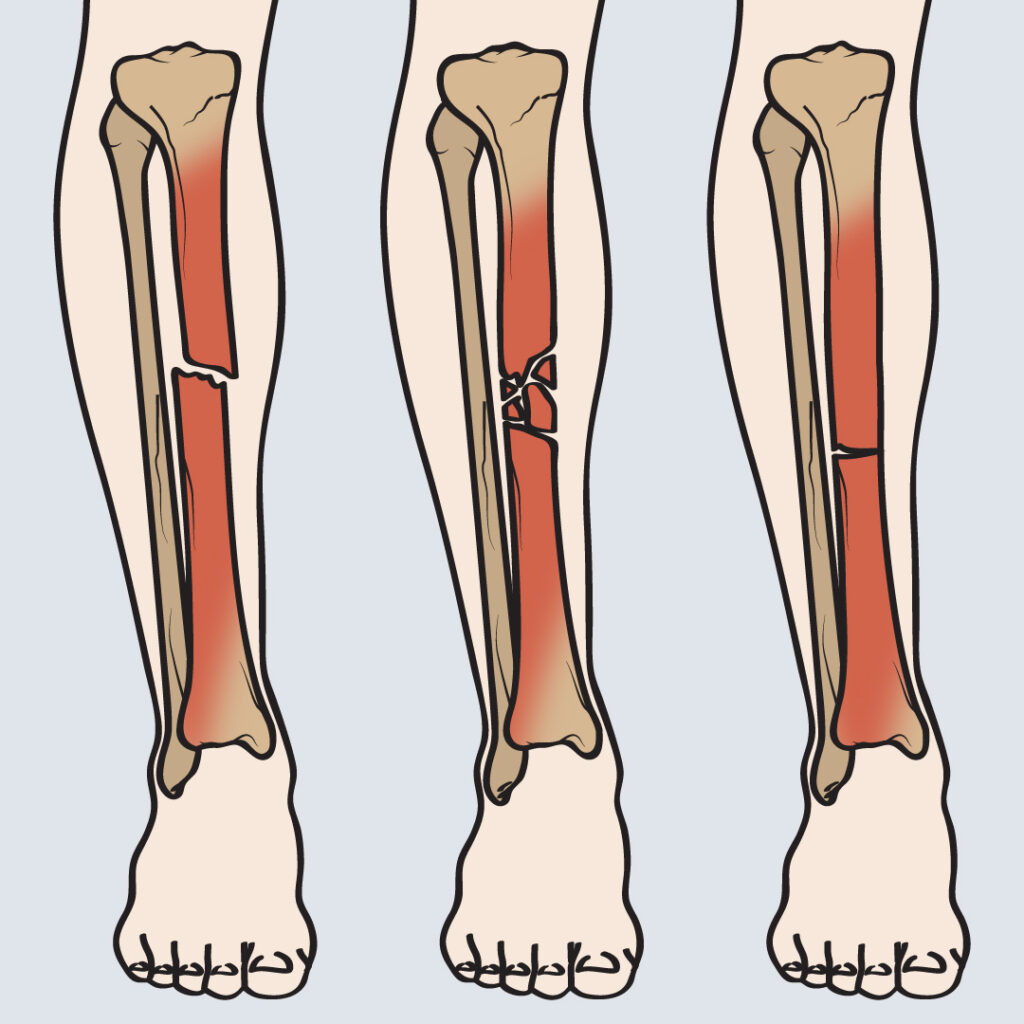

• Fraktur Kompresi

fraktur atau patah tulang yang disebabkan oleh tekanan vertikal (sesuai sumbu tubuh) yang cepat dan berat. Tekanan tiba-tiba tersebut dapat menekan tulang belakang sehingga tulang menjadi terjepit dan retak atau bahkan patah. Jika kekuatan yang menimpanya cukup tinggi, tulang belakang dapat hancur di saat yang sama, disebut burst fracture. Fraktur kompresi umumnya dialami oleh orang yang memiliki osteoporosis, tumor tulang belakang, atau kondisi tulang yang tidak sepadat orang normal.

• Burst Fracture

patah tulang belakang yang disebabkan oleh kekuatan yang tinggi, sehingga tulang belakang hancur seketika. Tidak seperti fraktur kompresi, burst fracture umumnya terjadi pada beberapa tulang belakang. Segmen tulang yang pecah dapat menyebar ke tempat lain sehingga menyebabkan kerusakan parah sumsum tulang.